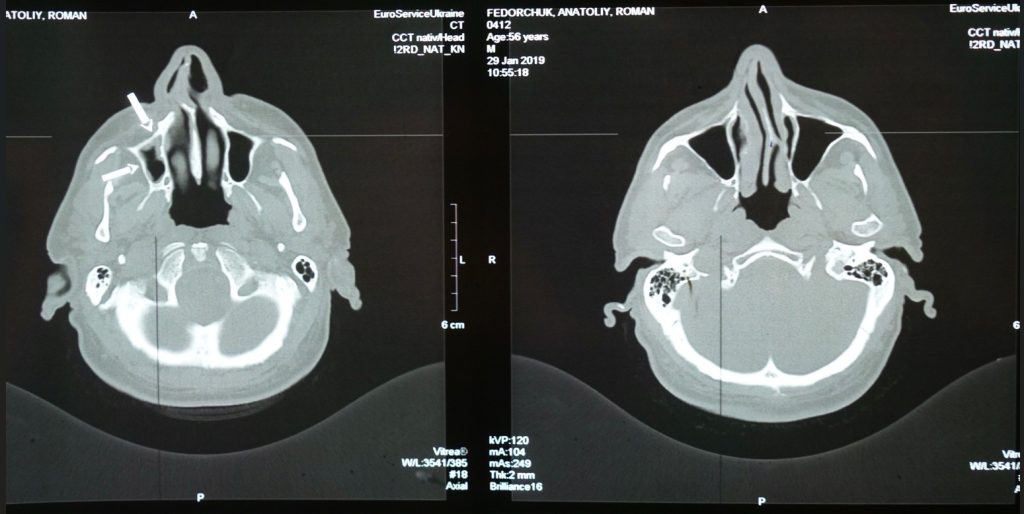

Il progetto pilota, promosso da Bracco Imaging in collaborazione con il partner tecnologico Zereau e che, insieme a CDI, coinvolge alcune strutture diagnostiche a livello europeo, nasce per affrontare una sfida ambientale sempre più rilevante per il settore sanitario: la presenza di mezzi di contrasto nelle acque reflue ospedaliere. Dopo esami diagnostici come TAC o risonanze magnetiche, infatti, i mezzi di contrasto vengono eliminati dall’organismo attraverso le urine dei pazienti, raggiungono i sistemi fognari e, successivamente, l’ambiente.

Per intercettare queste sostanze prima che vengano disperse nelle acque reflue, il progetto Re.Water prevede l’installazione di sistemi dedicati alla filtrazione delle urine dei pazienti sottoposti a esami con mezzi di contrasto iodati. I pazienti vengono invitati a rimanere nella struttura sanitaria per un breve periodo aggiuntivo dopo l’esame, per consentire l’eliminazione urinaria iniziale del mezzo di contrasto attraverso servizi igienici dedicati, dotati di dispositivi di filtrazione specifici. I filtri saturi vengono poi trattati in impianti specializzati che garantiscono il corretto smaltimento delle sostanze attive.